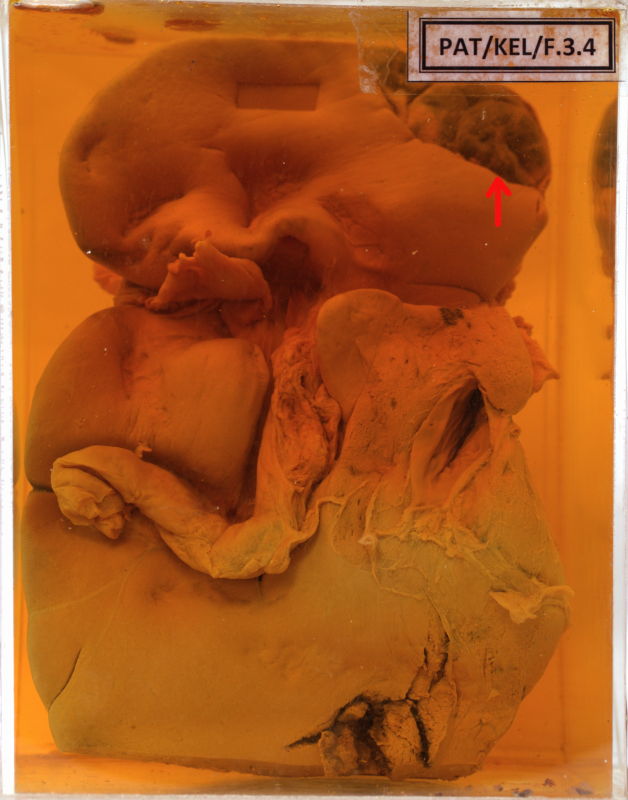

F.3.4 Haemangioma of liver

It looks pale.

Superiorly and superficially, on the diaphragmatic surface is a dark area, about 2 inches in diameter and well encapsulated by a fine membrane.

Small part of this has been opened in to and shows blood.